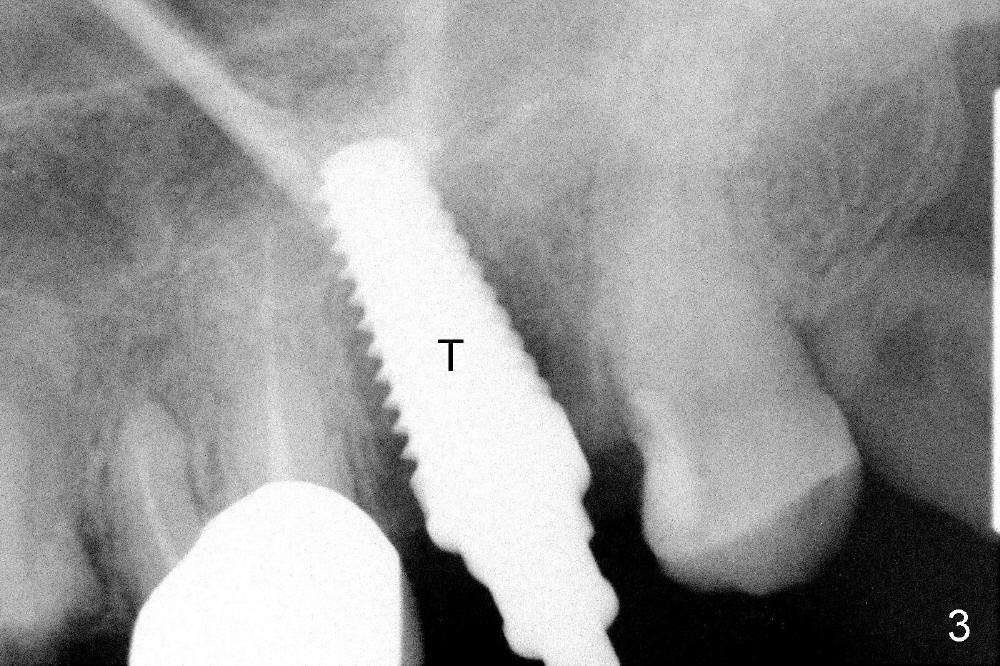

A 66-year-old lady requests restoring a broken tooth (Fig.1). Osteotomy is initiated in a thin septum (Fig.2 (occlusal mirror view) S) by sectioning, drilling and tapping (Fig.3 T). When 7x17 mm tap is removed, the osteotomy is found to form basically in the middle of socket (Fig.4 O). The apical portion of three sockets (Fig.5: MB, P and DB (not labeled) is packed with mixture of autogenous bone and allograft. When a 7x14 mm implant is placed, there are buccal and lingual gaps (Fig.6 *). The latter are bone grafted again (Fig.8 *) and require a coverage. After placement of a 4x3 mm abutment (Fig.7,8 A), an immediate provisional is fabricated (Fig.9 tissue surface view) to cover the remaining sockets (Fig.10 (occlusal mirror view), 11 (buccal view)). The provisional is infra-occlusal, i.e., load-free (Fig.11). The buccal and lingual aspects of the socket are covered by fresh epithelium 8 days postop (Fig.12 <). The implant appears to have osteointegrated 4 months postop (Fig.13). The tooth #16 appears to have shifted mesially. It is difficult to prepare for #15 crown. Luckily the patient agrees to have it extracted because of persistent sensitivity after MO composite. The definitive crown at the site of #15 is cemented 6 months postop (Fig.14).